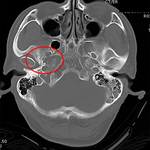

Comminuted nondepressed fracture

From the teaching collection of Demetrios Demetriades; used with permission